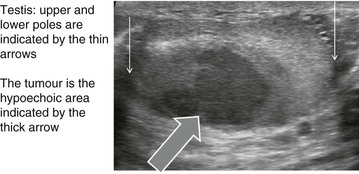

Seminomas: More than half of malignant testicular tumours are seminomas, derived from spermatocytes (Fig. 33.6). They occur predominantly between the ages of 20 and 45 with a peak incidence at 35 years. The cut surface of a seminoma is typically pale, creamy-white and homogeneous. Histologically, tumour cells are uniform and tightly packed. A distinct but rare form of seminoma, spermatocytic seminoma, occurs between the ages of 50 and 70 years and almost never metastasises.

A malignant testicular tumour usually presents as a painless, progressively enlarging testicular lump. If the testicular capsule becomes involved, a secondary hydrocoele may appear but this is usually small and does not hinder palpation.

A solid testicular lump must be assumed to be a tumour until proven otherwise. The history is rarely helpful but may include an episode of trauma which merely drew attention to the lump. On examination, the testis is either diffusely enlarged or contains a discrete lump which is firm and non-tender. Systemic examination may reveal evidence of metastases. Malignant cervical nodes may be palpable but inguinal nodes are not involved unless the tumour has spread to scrotal skin, which is rare except when biopsy or orchidectomy has been performed through a scrotal incision. Orchidectomy for suspected tumour should always be carried out via an inguinal approach.

The first investigation is scrotal ultrasonography. If this confirms a solid testicular mass, surgical exploration is required. Preliminary staging investigations are usually performed next, including chest X-ray or CT (to look for hilar node involvement and lung secondaries), CT abdomen and pelvis to assess retroperitoneal nodes and blood levels of tumour markers (which must be measured before treatment). A standard method of staging testicular tumours is shown in Figure 33.7 and Box 33.4. Tumour markers contribute to diagnosis and staging and are useful for tracking residual or recurrent metastases because blood levels correlate with tumour bulk. Serial postoperative measurements help monitor disease progress and the impact of therapy.